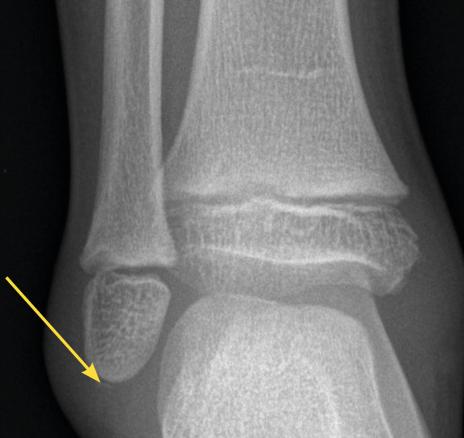

Avulsion de la pointe de la fibula

Avulsion de la pointe de la fibula  chez un garçon de 8 ans avec œdème latéral.

Extrait de : Entorse de cheville de l’enfant